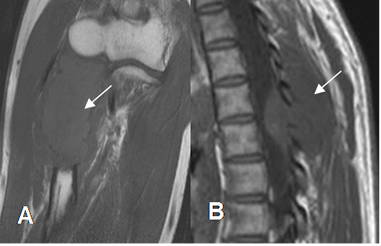

Fig 3. Medula ósea en adulto normal

A: RM sagital en T1 y B: RM sagital en STIR. La señal de la medula osea amarilla (Flecha delgada), es similar a la de la grasa (Flecha gruesa).